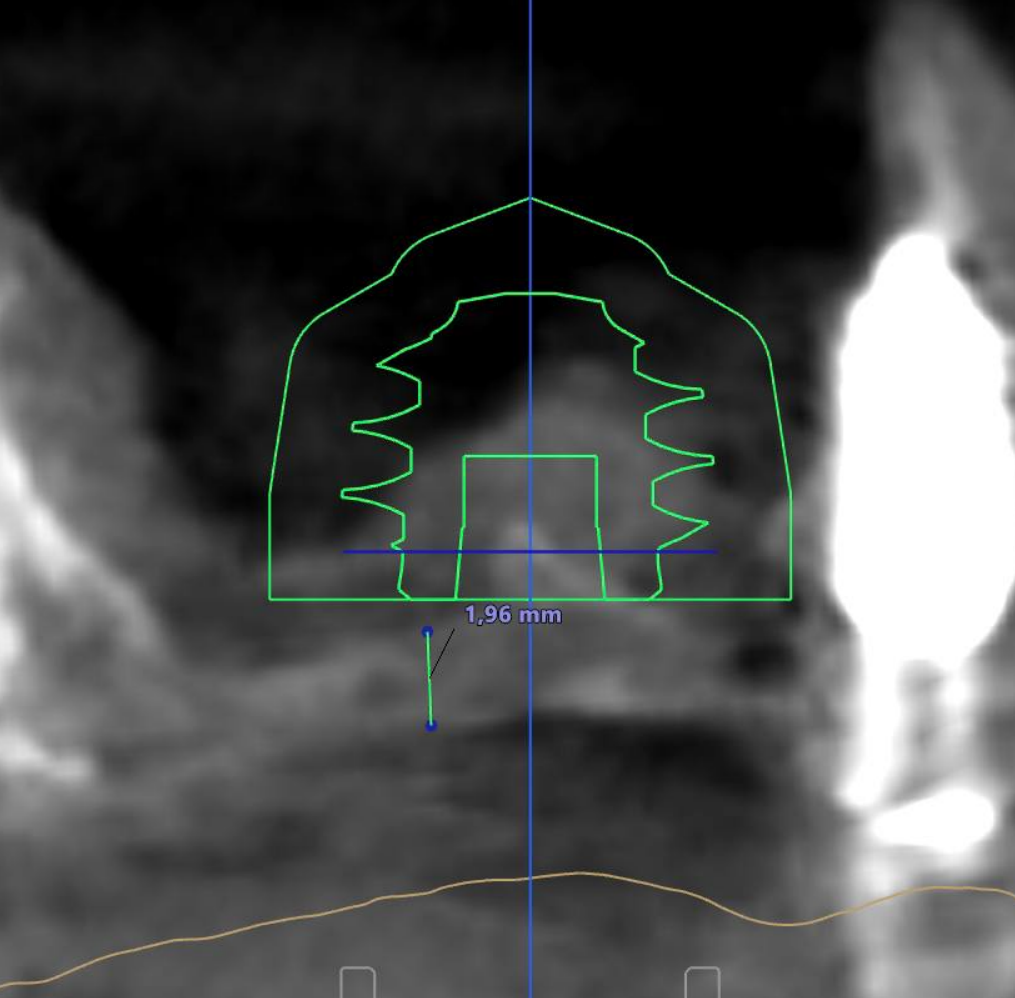

Изначально по данным КТ планировался открытый синус-лифтинг – операция сложная, особенно в зоне перегородки, где высок риск перфорации шнейдеровой мембраны.

Закрытый синус-лифтинг в области перегородки. Время операции сокращено до 15 минут, вместо стандартного протокола. Значительно меньшее время до нагрузки импланта, чем при открытом синус-лифтинге.

Для данного кейса выбран имплантат AnyRidge 7,5 x 7,0 мм. Торк при внедрении был 16 Н/см, но ISQ = 50 ед.!

Виртуальное планирование и хирургический шаблон в данном случае – не просто удобный инструментарий, а критически важные аспекты для:

• Безопасности (уменьшить риск перфорации мембраны)

• Скорости (операция проходит значительно быстрее)

• Комфорта пациента (сокращается восстановительный период)